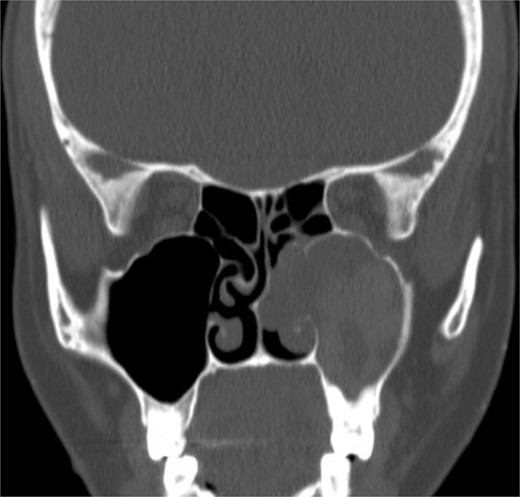

Isolated maxillary allergic fungal sinusitis

A 37-year-old female with a history of bronchial asthma, complained mainly of chronic headache, left sided facial pain, which was associated with persistent post-nasal drip. Endoscopic examination showed left-sided tenacious discharge filling the middle meatus with grade two polyps. NCCT (Fig. 5) showed left isolated heterogenous maxillary sinus opacity suggestive of allergic fungal sinusitis. She underwent endoscopic sinus surgery (Fig. 6) with removal of fungal mucin and mud, complete left maxillary sinus aeration was ensured. The patient was free of symptoms during her 1 week follow up.

Coronal NCCT image of the paranasal sinuses showing isolated left complete heterogenous maxillary sinus opacification with obstructed left osteomeatal complex.